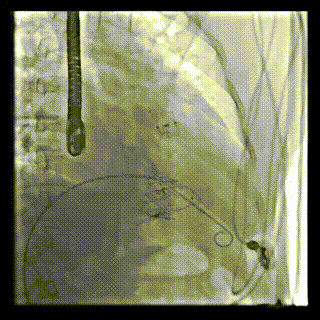

三例患者入院后,葛均波院士團(tuán)隊周達(dá)新教授、潘文志教授、張源博士、陳莎莎博士及心超室的潘翠珍教授、李偉教授對患者的情況進(jìn)行詳細(xì)評估和討論,最終決定為三例患者選擇LuX-Valve Plus40mm、50mm和50mm型號的瓣膜進(jìn)行手術(shù)治療。手術(shù)后即刻拔除氣管插管,術(shù)后患者三尖瓣反流癥狀得到顯著改善,復(fù)查心超結(jié)果顯示人工三尖瓣瓣膜支架固定穩(wěn)定,瓣葉關(guān)閉形態(tài)未見異常,未見明顯反流。